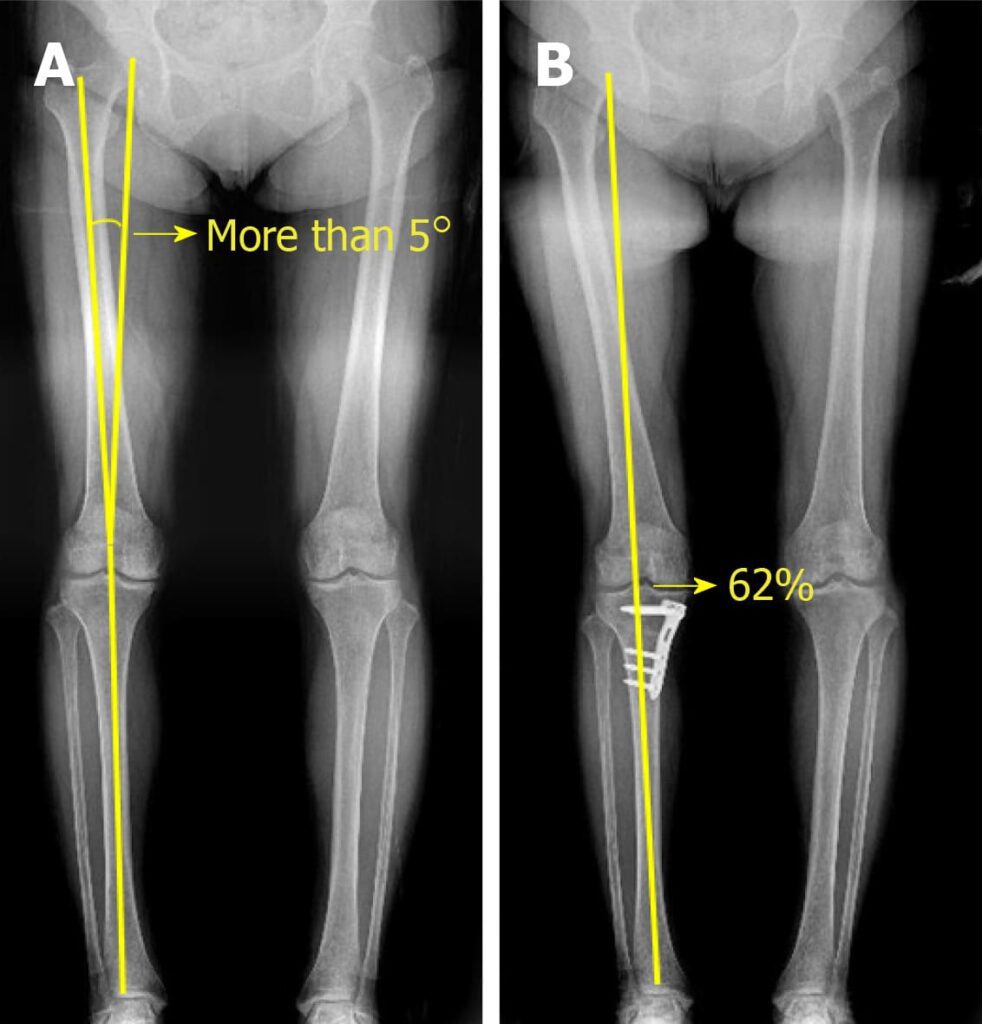

Arthroscopic comparison of knee cartilage before treatment and during follow-up after high tibial osteotomy combined with implantation of umbilical cord blood-derived mesenchymal stem cells. This indicates that the treatment helped the damaged cartilage areas begin to fill in with new tissue, which may contribute to improving joint function.

doi.10.4252/wjsc.v12.i6.514